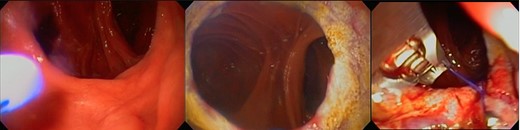

Revisional bariatric surgery is performed with the patient in french position by a bariatric surgeon with many years of experience. During the bowel exploration, we found an alimentary limb of 80 cm, a biliopancreatic (BP) limb of 40 cm and a common channel of 625 cm (Fig. 1). A distalization of the BP limb was performed, using a blue load to resect the intestinal segment of the alimentary limb proximal to the jejunojejunal anastomosis. Posteriorly, we began to measure the common channel to create the new jejunojejunal anastomosis at 320 cm of the ileocecal valve distalizing the BP limb to 340 cm and shortening the common channel to 320 cm (Fig. 2). Afterward, assessing via endoscopy a gastric pouch of 5 cm is measured with a large non-functional limb (jejunal cane) and a stoma size of 30 mm, it is decided to perform eTOR procedure using the OverStitch™ platform, reducing the stoma size from 30 to 10 mm approximately (Fig. 3). Both procedures last 200 min without complications. The patient was discharged after 48 h under nutritional indications. Ten months after surgery the patient has lost 31.7 kg with a BMI of 32.60 kg/m2 without eventualities, taking nutritional supplements.

eTOR procedure: (a) view of the GJ anastomosis, (b) APC therapy and (c) eTOR.